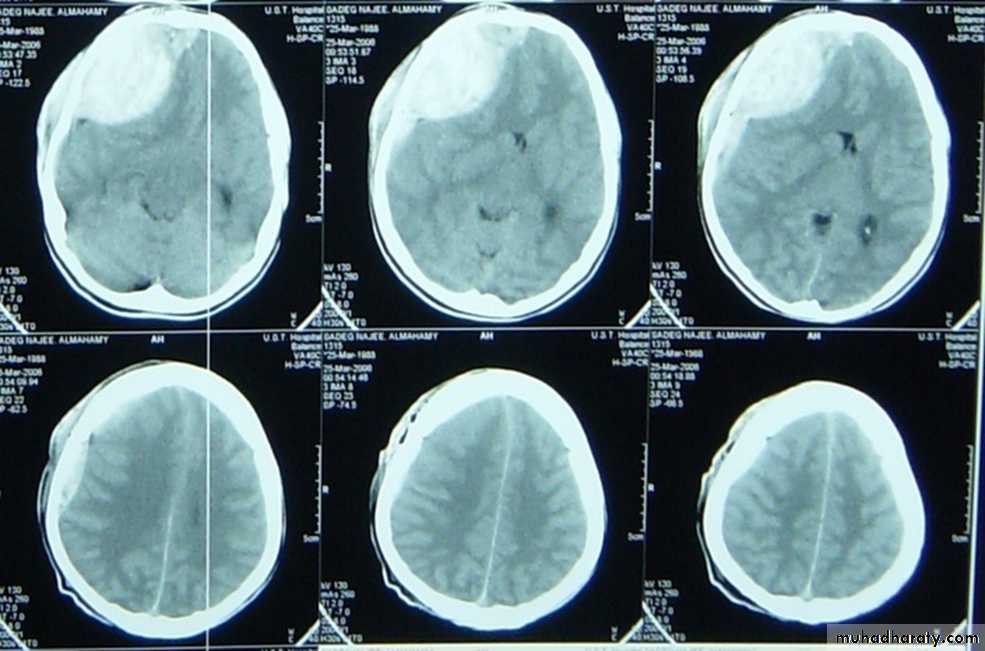

Mostly occurs in those over 50 years old,½ of patients have got no history of trauma (If there is any history of trauma then it is trivial), Alcoholism, epilepsy, coagulopathy are common, Dementia is common presentation. The treatment is medical In minimal neuological deficit. If not successful or with deterioration of neurological picture so surgery is the role by burr hole evacuation.( the CT picture is hpodense crescent exraaxial mass)Extradural hematomas

Mostly resulting from meningial vessel tear (arteries > Veins > sinuses) and Fractures are common associated injury. Severe associated brain injury is rare. Usually the Level of consciousness is variable(lucidity interval is common). The haematoma with mass effect must be evacuated within ½ hour. if small follow up is recommended. The Prognosis depends on level of consciousness at time of presentation ( C picure is that of biconvex or lense hyperdense exrtracranial mass)

CT scan : almost without exception , an unenhanced (i.e.- non – contrast ) CT scan of brain suffices for patients seen in emergency department presenting after trauma or with new neurological deficit .The main emergent conditions to rule out :

1. blood ( hemorrhages or hematomas(

a. EDH ( extradural hematoma (

b. SDH ( subdural hematoma (

7. shift of midline structures